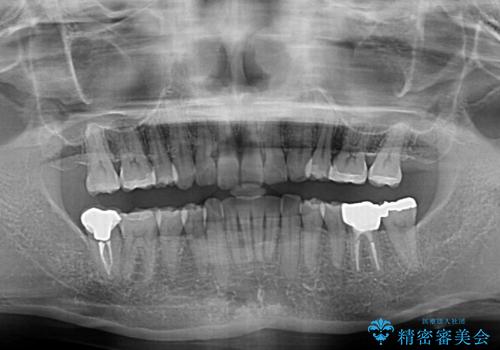

- 以前行った抜歯矯正が後戻りし、開いてしまったスペースが気になるとのことで来院された患者様です。

インビザラインを用いて開いてしまったスペースと前歯のデコボコを改善することとしました。

矯正治療後には気になっていた銀歯をセラミッククラウンやセラミックインレーにて治療することとしました。

上顎前歯を左右対称となるように歯列を整えたいとのことでしたが、すり減って形態が大きく異なっていたため、できる範囲での仕上がりとなりました。